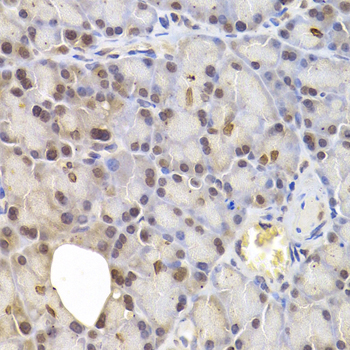

• A6246: image 3

Immunohistochemistry of paraffin-embedded human colon cancer using IRF6 antibody at dilution of 1:200 (400x lens).